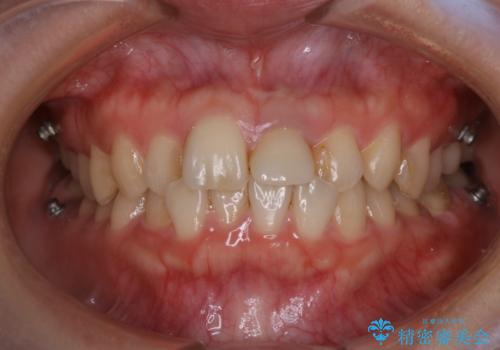

インビザラインのアタッチメントをつける前にPMTC

- インビザラインでの矯正治療中で、アタッチメントの設定前にきれな状態にしたいとのことでした。PMTC30分コースを行いました。

マウスピース矯正インビザライン治療では、歯の表面にアタッチメントという突起を設定します。(アタッチメントは歯の動きを効率的に移動するためのものです)

アタッチメントの設定時に、プラークや歯石・着色がついていると精密に付かないことや、外れやすくなることがあります。

PMTCを行い、専門的な機械でしっかりと汚れを除去してからアタッチメントの設定をすることがおススメです。